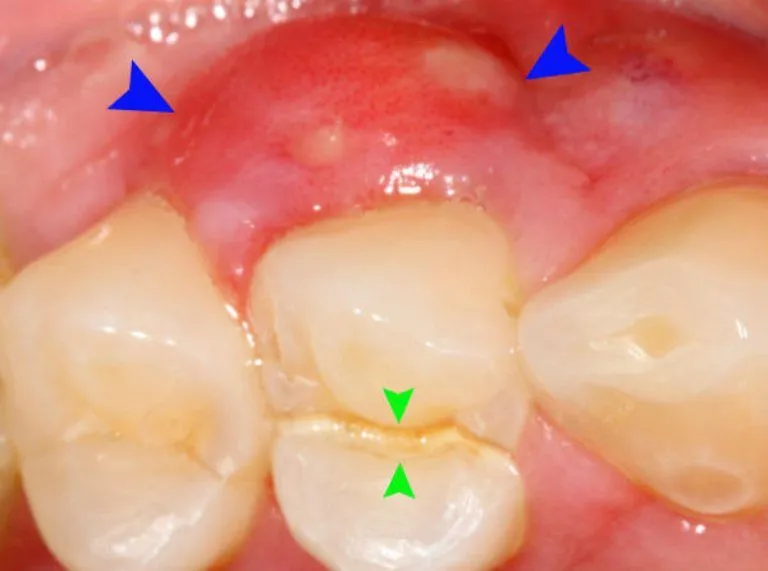

Viêm lợi răng hàm không phải là hiện tượng hiếm gặp. Người lớn và người cao tuổi có nguy cơ cao hơn do thói quen ăn uống,

Sưng lợi là tình trạng phổ biến mà nhiều người gặp phải trong cuộc sống hàng ngày. Đây không chỉ gây đau nhức và khó chịu mà

Tình trạng bị sưng lợi chân răng không còn xa lạ với nhiều người, từ trẻ em đến người lớn. Mặc dù đôi khi chỉ là một

Nướu sưng (hay còn gọi là sưng lợi) là một tình trạng răng miệng khá phổ biến, gây ra không ít phiền toái và đau nhức cho